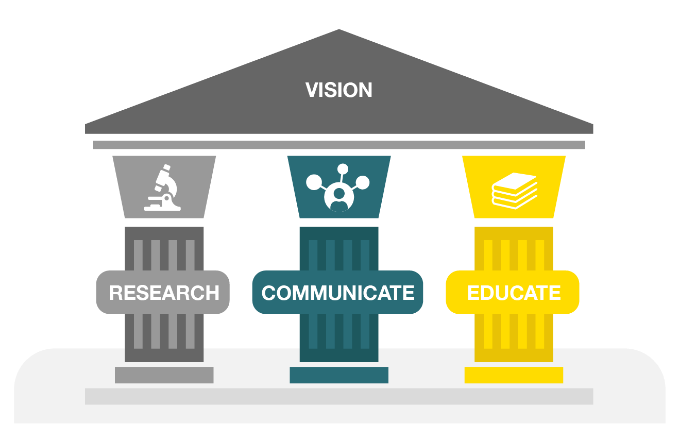

The original goal of the initiative was to understand the needs of pain patients and develop solutions to improve the management of pain. Since its inception, CHANGE PAIN has therefore focussed on the following three areas: Research (patient and physician surveys), publications (in journals such as the CMRO) and education (on pain physiology and treatment options using various eLearning modules and eBooks).

RESEARCH

Generate actionable insights into patients’ and HCPs needs

Generate new evidence on pathophysiology and management of pain

COMMUNICATE

Communicate findings in scientific publications

Disseminate the latest scientific findings and information

Inform clinical decision making

EDUCATE

Improve knowledge on pain physiology, diagnosis, and management among healthcare professionals

Improve knowledge on patients’ self-management

Translate scientific information for patients